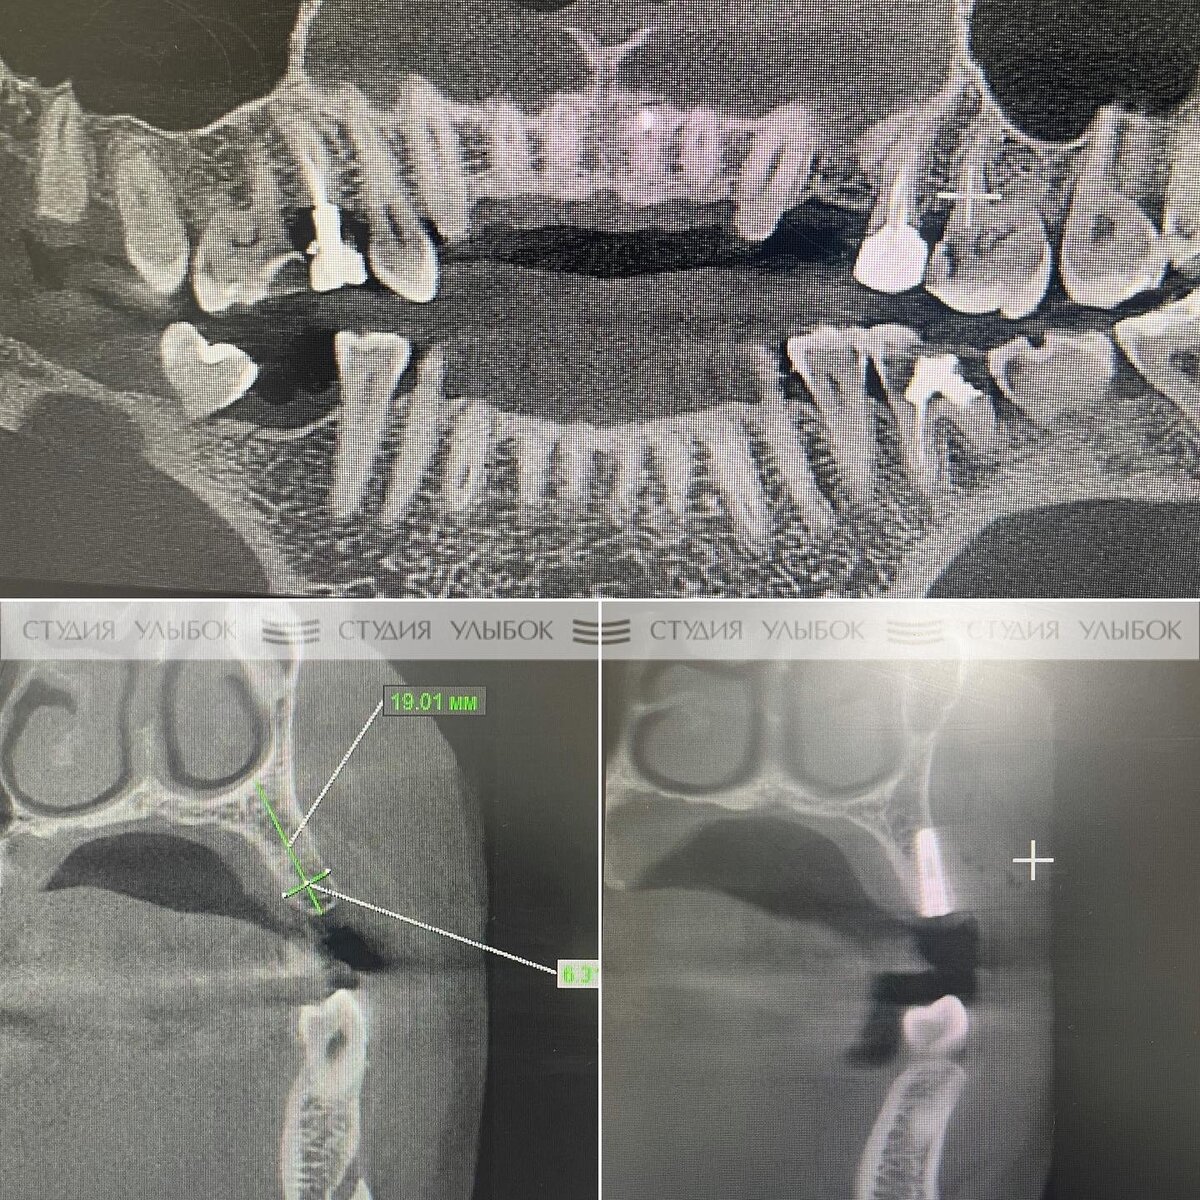

Клинический случай по классической установке имплантата позиции зуба 2.4

Пациент обратился по поводу имплантации отсутствующего зуба 2.4. Зуб был удален несколько лет назад. Исследования Компьютерной томографии (#КТсочи) показала, что из возможных вариантов восстановления зуба целесообразно использовать классический вариант имплантации, т.к. в другом случае пришлось бы препарировать при этом здоровые ткани рядом стоящих зубов 2.3 и 2.5 и устанавливать 3 коронки с мостом над зубом 2.4. КТ показало, что костной ткани челюсти в позиции зуба 2.4 достаточно по объёму. Была проведена операция по имплантации, включая все необходимые этапы: - постановку анастезии, - разрез десны, - формирование ложе под имплантат, - установку имплантата, - установку винта заглушки, - ушивание пародонта. Через 10-12 дней мы сняли швы. На фото мы показываем, как выглядит десна спустя 3 недели. Сроки интеграции (приживления) имлантатов для верхней и нижней челюсти различаются. Имплантаты верхней челюсти можно протезировать через 6 месяцев, нижней челюсти, через 4-4,5 месяца. Спуст

Зуб был удален несколько лет назад. Исследования Компьютерной томографии (#КТсочи) показала, что из возможных вариантов восстановления зуба целесообразно использовать классический вариант имплантации, т.к. в другом случае пришлось бы препарировать при этом здоровые ткани рядом стоящих зубов 2.3 и 2.5 и устанавливать 3 коронки с мостом над зубом 2.4.

КТ показало, что костной ткани челюсти в позиции зуба 2.4 достаточно по объёму. Была проведена операция по имплантации, включая все необходимые этапы: